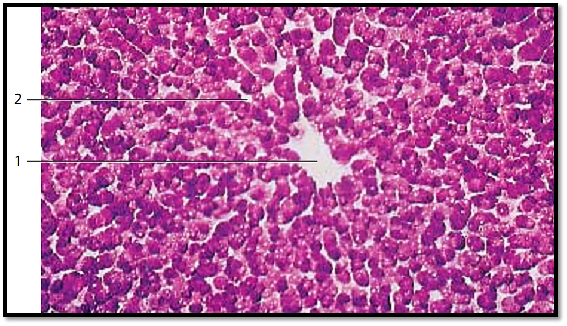

Glycogen , a large glucose polymer, is a frequently observed paraplasmic inclusion. It can be found in the cytoplasm of many cells in the form of fine or coarse granules. This figure shows the central region of a liver lobule. The center represents a cut through the central vein 1 . The red stain in the radially oriented liver cells corresponds to glycogen particles. Between the cells are the liver sinusoids 2 . Note the uneven distribution of the glycogen granules . The liver cell nuclei are not stained. It should also be noted that glycogen particles are not stained in routine histology preparations. With hematoxylineosin (HE) staining, they leave small empty spaces in the red-tinged cytoplasm. However, their identification can successfully be accomplished with the Best carmine stain and the periodic acid-Schiff (PAS) reaction.

1 Central vein of a liver lobule

2 Liver sinusoids